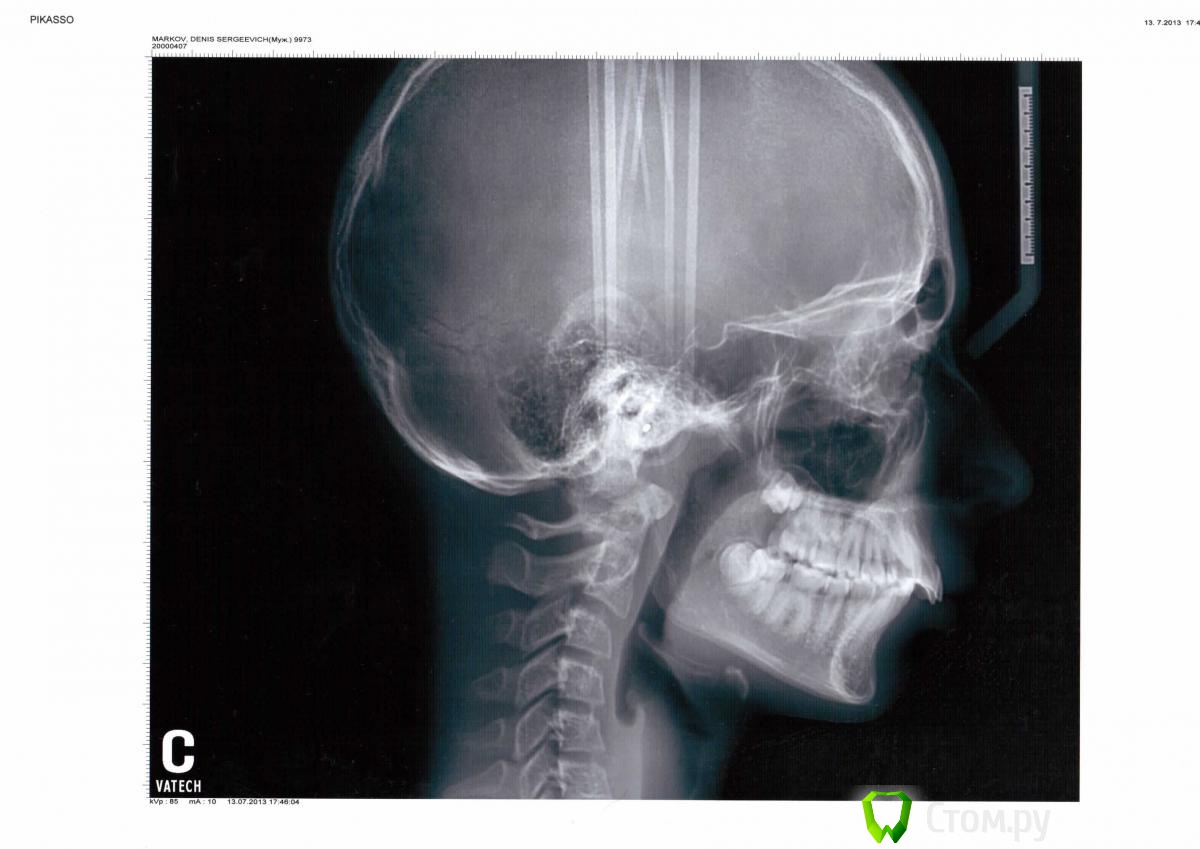

Force Опубликовано 16 января, 2014 Поделиться Опубликовано 16 января, 2014 Нижняя челюсть в ретропозиции, нижняя микрогнатия. Дефицит места для прорезывания зубов мудрости. Избыточный наклон нижних зубов. Двойная окклюзионная плоскость. Это все показания для удаления нижних зубов мудрости. Доктора лучше поставить в известность, но думаю она и сама рада будет. Верхние восьмерки не критичны для дистального прикуса, и расположены они весьма высоко - не достать без серьезного вреда. А нижние - близко и без корней- заживет быстро, если хирург опытный 1 Ссылка на комментарий

Ayrat_zub Опубликовано 27 января, 2014 Поделиться Опубликовано 27 января, 2014 (изменено) Спустя полдня уже заметны щели между зубами и сын постоянно говорит, что эти зубы болят. Значит, пружина работает. Радоваться ли нам этому факту? И ещё вопросик появился. Возможно ли вместо удаления премоляров слегка сточить по бокам все верхние зубы и стянуть их? Это же тоже каким-то образом уменьшит верхнюю челюсть? Она сказала, что верх.чел."великовата". Или стачивание по пагубности воздействия идентично удалению?Ещё прочитала, что для расширения нижней челюсти можно использовать какие-то пластины с винтами, аппарат "бампер" и др., или это только в раннем возрасте, а нам поздно? Не лучше ли их использовать? Метод с расширением пространства между зубами меня сильно смущает, почему то за корни их переживаю...(Извините, если глупость какую написала... )Судя по ТРГ, рост скоро пройдет свой пик, так что корректор(Форсус или любой другой) надо уже делать, при неудаче, вы я так понял готовы на хирургическую коррекцию?) Изменено 27 января, 2014 пользователем Ayrat_zub 1 Ссылка на комментарий